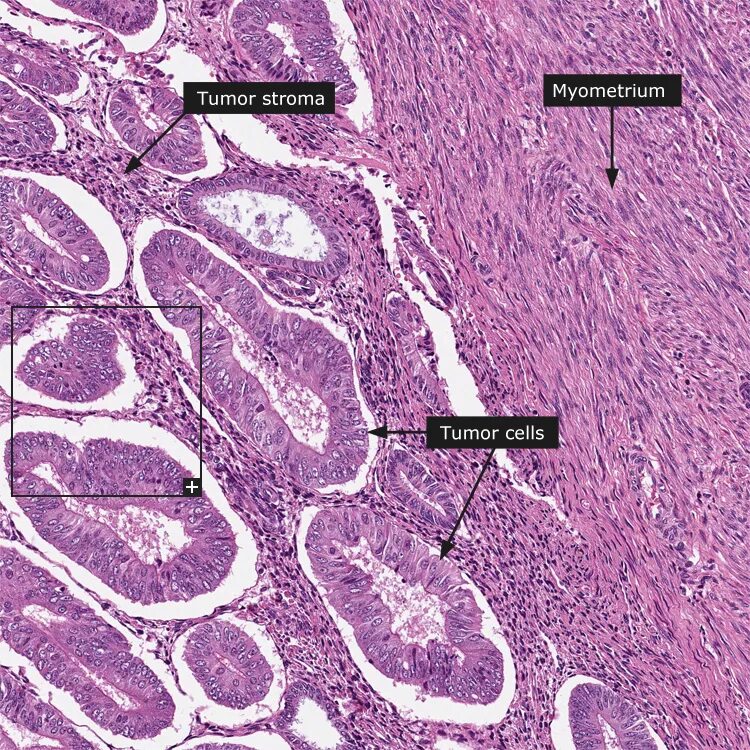

Эндометрий гистология